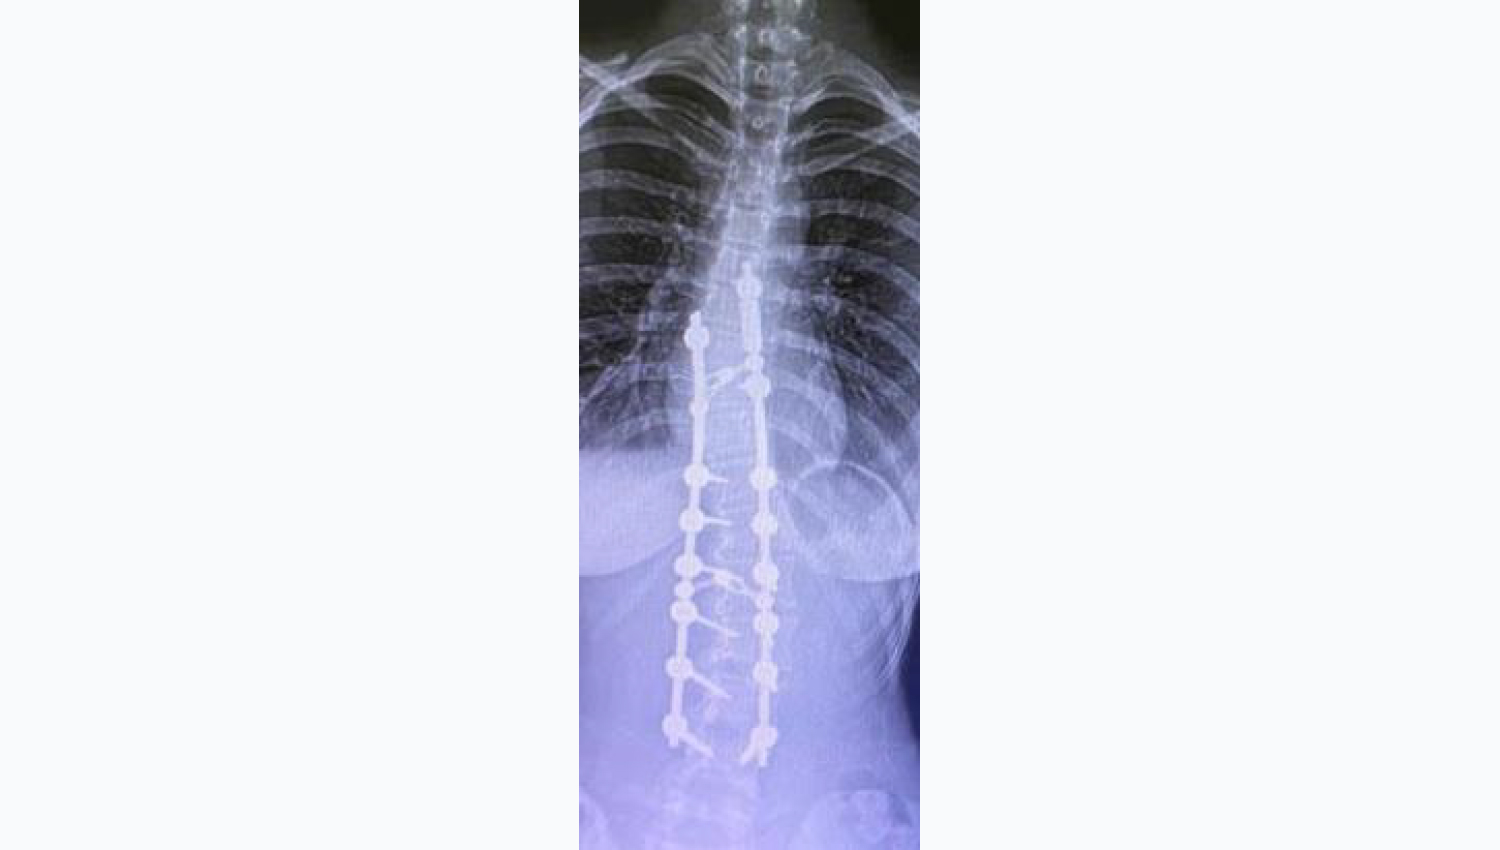

2.In order to treat scoliosis, Metrosan- Ligamed Cannulated Posterior Polyaxial Screws(40x40, 40x45, 40x50) areimplanted. After this implantation, the Powerbone Flexible Graft product is placed in the field.

3.Final radiological view.